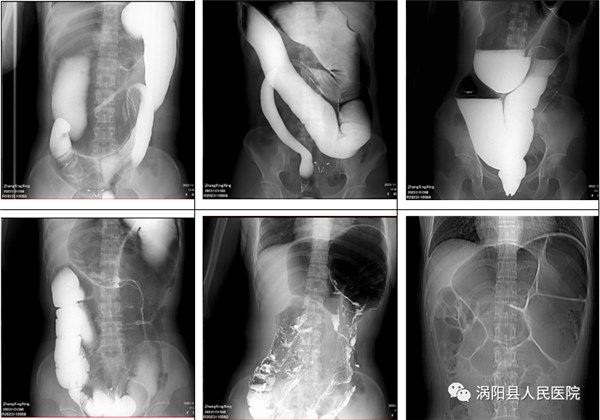

但住院期间,胃肠外科席如光主任发现张女士并不是简单的结肠扭转,而是继发性巨结肠导致大便无法顺利排出,导致结肠扭转,所以才出现了上述症状。住院期间的钡剂灌肠证实了这一点。

图中白色物质为钡剂

(右侧为病变肠道)